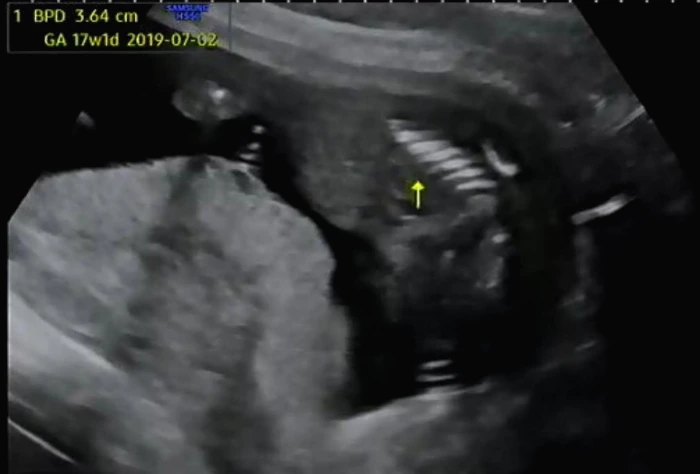

BPD(태아의 머리둘레)와 AC(태아의 복부둘레)를 측정하고 이후 심장소리를 확인했다. BPD와 AC로 이용하여 주수에 맞게 잘 자라고 있는지 확인했다. 아기는 여전히 잘 자라고 있다고 일정하게 심장소리를 들려주며 초음파 상으로 열심히 움직이고 있었다.